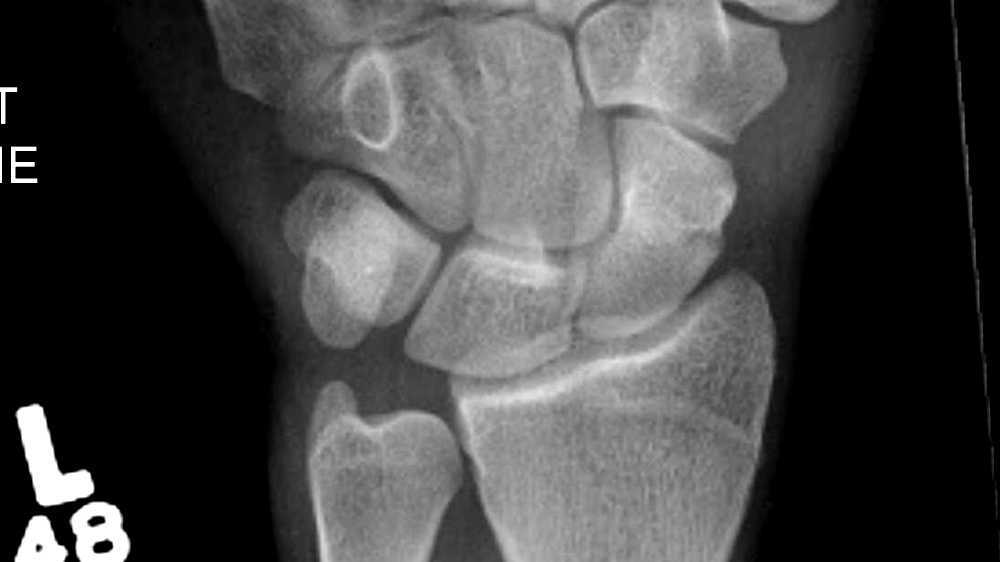

Scaphoid Fracture Complications Symptoms scaphoid fracture is a break in the scaphoid bone, one of the small bones in your wrist. scaphoid fractures are the most common carpal bone fracture, often occurring after a fall onto an outstretched hand. symptoms of a scaphoid fracture typically include swelling and pain in the wrist just below the base of the thumb. in some cases, a scaphoid fracture can lead to complications, including the following: scaphoid fracture is a break in the scaphoid bone, one of the small bones in your wrist. Most people with a scaphoid fracture (which is the same as a broken wrist) will have pain and/or. Symptoms can include pain and swelling. a scaphoid fracture is usually caused by a fall on to an outstretched hand. It can develop if there is reduced blood. Breaks are often caused during falls or as a result of repeated use of the wrist in sports such as. axial loading of the wrist in forced hyperextension and radial deviation can cause the fracture as the scaphoid impacts on the dorsal rim. A bone that does not heal is called a nonunion.

LearningRadiology Avascular, Necrosis, Scaphoid, AVN, navicular Scaphoid Fracture Complications Symptoms Symptoms can include pain and swelling. axial loading of the wrist in forced hyperextension and radial deviation can cause the fracture as the scaphoid impacts on the dorsal rim. in some cases, a scaphoid fracture can lead to complications, including the following: It can develop if there is reduced blood. symptoms of a scaphoid fracture typically include. Scaphoid Fracture Complications Symptoms.